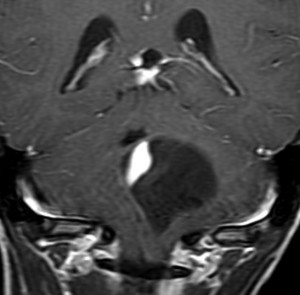

18歳で発症して,60歳まで無治療の大きな視床下部毛様細胞性星細胞腫

hypothalamic pilocytic astrocytoma

1968年 18歳の時に頭痛嘔吐で発症しました。第3脳室腫瘍と閉塞性水頭症の診断だけで,シャント手術を受けました。手術も化学療法も放射線治療もされていません。下の画像は60代で撮影されたものです。この例では,第3脳室内に増大した大きな毛様細胞性星細胞腫が,視床下部下垂体障害を出すことなく,自然経過で増大停止 growth arrest して,カチカチに固まってしまうということを教えてくれます。でも,こんなに都合よく経過観察できる例も珍しいです。

CTでは強い石灰化があります。右のT2強調画像では腫瘍は等信号,視交叉の後ろにあります。内部の低信号は石灰化です。

T1強調画像では等信号,ガドリニウム増強でごく一部がまだらに増強されます。